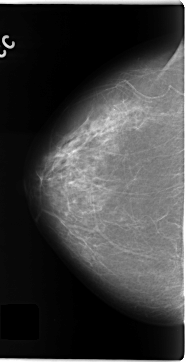

C_0135_1.RIGHT_CC

RIGHT_CC LINES 4704 PIXELS_PER_LINE 2408 BITS_PER_PIXEL 12 RESOLUTION 50 NON_OVERLAY